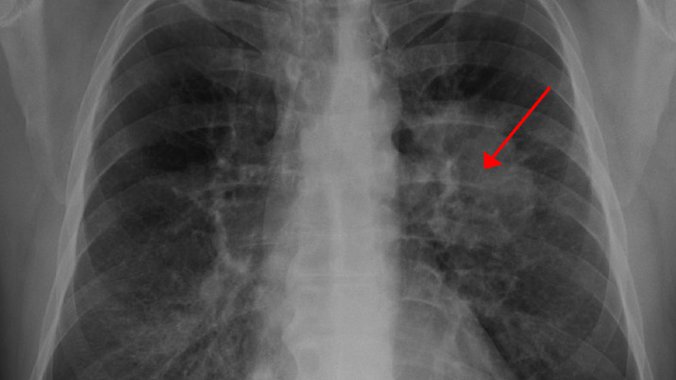

Institut za plućne bolesti Vojvodine dobio je najsavremeniju terapiju za lečenje raka pluća, a prva pacijentkinja već je započela lečenje.

Načelnik Odeljenja za dijagnostiku i terapiju karcinoma bronha i Centra za klinička ispitivanja Klinike za pulmološku onkologiju Instituta za plućne bolesti Vojvodine, Bojan Zarić, kaže da je reč o revoluciji u lečenju raka pluća.

- Reč je o revolucionarnoj terapiji karcionoma pluća, s izuzetno uspešnim rezultatima koje niko nije očekivao - rekao je Zarić, povodom početka primene nove, savremene terapije u lečenju raka pluća, piše novosadski "Dnevnik".

- Rezultati su pokazali da prvi put imamo 20 odsto pacijenata s metastatskim rakom pluća, koji žive duže od pet godina, a do sada je takvih pacijenata bilo od jedan do dva odsto. Najnovija istraživanja pokazala su da je preživljavanje 30 meseci, odnosno dve i po godine, a pre ove terapije to je bilo od sedam do devet meseci. Ovaj lek je zaista revolucija u lečenju raka pluća - naveo je Zarić.

Prema učestalosti raka pluća, Srbija je druga u Evropi, odmah posle Mađarske.

Samo u Institutu iz Sremske Kamenice svake godine bude dijagnostifikovano 1.200 novoobolelih od raka pluća svih formi, što je stotinu mesečno.

U cijeloj Vojvodini godišnje ima oko 1.500 novih slučajeva nekog od oblika raka pluća.

Nesitnoćelijski karcinom bronha ima oko 1.000 pacijenata, njih oko 200 ima sitnoćelijski, a ostali imaju druge vrste raka pluća.